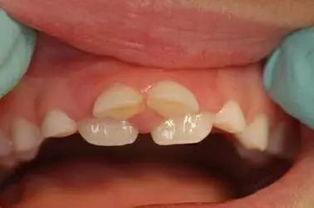

现在,让我们来看看这个视频吧!视频中,一位专业的口腔医生详细讲解了成人双排牙恢复的过程。首先,医生会通过X光片检查牙齿情况,确定治疗方案。根据具体情况,医生会采取不同的矫正方法。